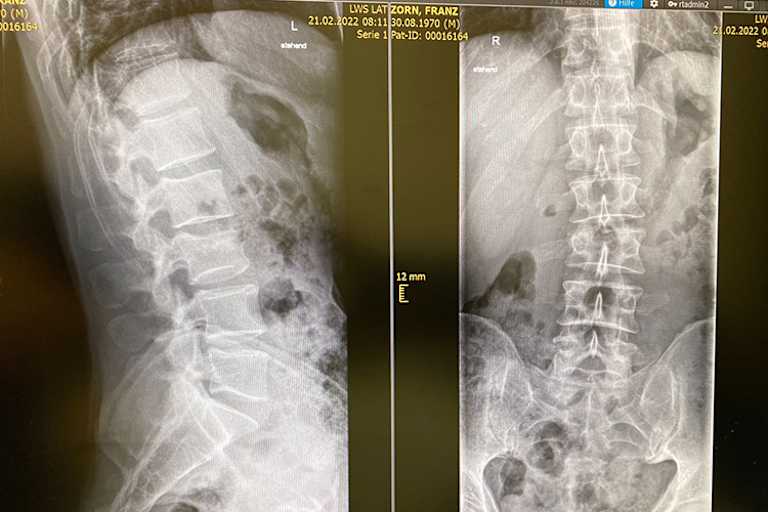

"Ich war gut für die EM vorbereitet. Im Training fühlte ich mich sehr gut und im Rennen lief alles auf Podiumskurs", meldete sich Zorn am Montag zu Wort. "Im dritten Lauf hat mich in Führung liegend ein schwedischer Kollege vom Motorrad geholt und ich stürzte diesmal so schwer, dass ich nicht mehr richtig stehen konnte." Zorn gab mit sieben Punkten auf dem Konto auf und ließ sich zuhause im Krankenhaus genauer untersuchen: "Es wurde eine CT gemacht, leider bekam ich keine glückliche Diagnose: Ich habe mir den dritten Lendenwirbel gebrochen." Ob Zorn bei den kommenden Rennen in der Welt- und Europameisterschaft im März und April antreten kann, ist offen.